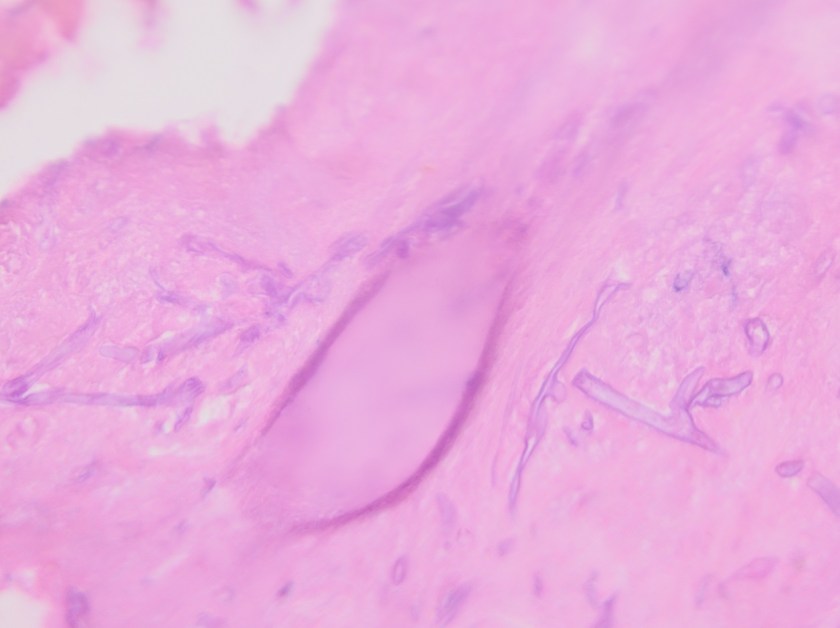

If a Mucorales is suspected, tissue specimens obtained during a surgical procedure should be sent for frozen section, direct examination with calcofluor white/KOH and fungal culture. On histologic exam or microscopic exam in the microbiology laboratory, the hyphae of Rhizopus spp. are wide & ribbion-like with few to no septations (pauci- or aseptate) and wide angle branching (90°) (Image 1). Further classification requires culture.